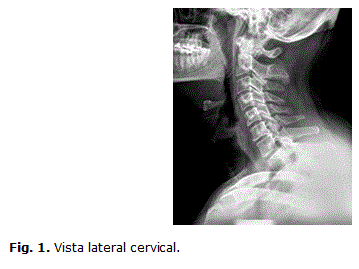

Sindrome De Klippel Feil Una Cervicalgia Poco Frecuente Medicina De Familia Semergen